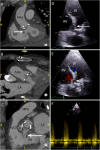

Infective Endocarditis (IE) remains a significant health challenge. Despite an increasing awareness, mortality is high and has remained largely unchanged over recent decades. Early diagnosis of IE is imperative and to assist clinicians several diagnostic criteria have been proposed. The best known are the Duke criteria. Originally published in 1994, these criteria have undergone significant modifications. This manuscript provides a timeline of the successive changes that have been made over the last 30 years. Changes which to a large degree have reflected both the evolving epidemiology of IE and the proliferation and increasing availability of advanced multi-modality imaging. Importantly, many of these changes now form part of societal guidelines for the diagnosis of IE. To provide validation for the incorporation of cardiac computed tomography (CT) in current guidelines, the manuscript demonstrates a spectrum of pictorial case studies that re-enforce the utility and growing importance of early cardiac CT in the diagnosis and treatment of suspected IE.